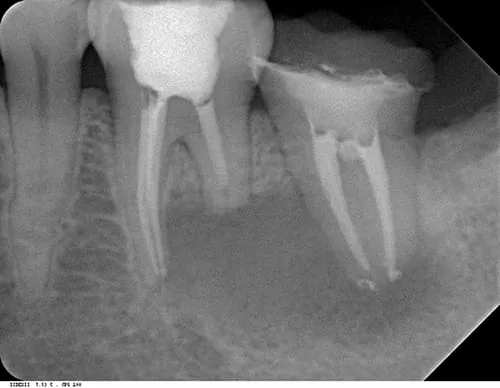

術前 全口X光片

- 左下臼齒區域 (圈選處) 出現巨大病灶且造成左下第一大臼齒 (箭頭處) 牙根吸收,牙髓神經部分壞死。

- 左下第二大臼齒(星星處)舊有根管治療未達理想,也受病灶侵犯。

(2) 根尖X光片

術前 (左下第一大臼齒)